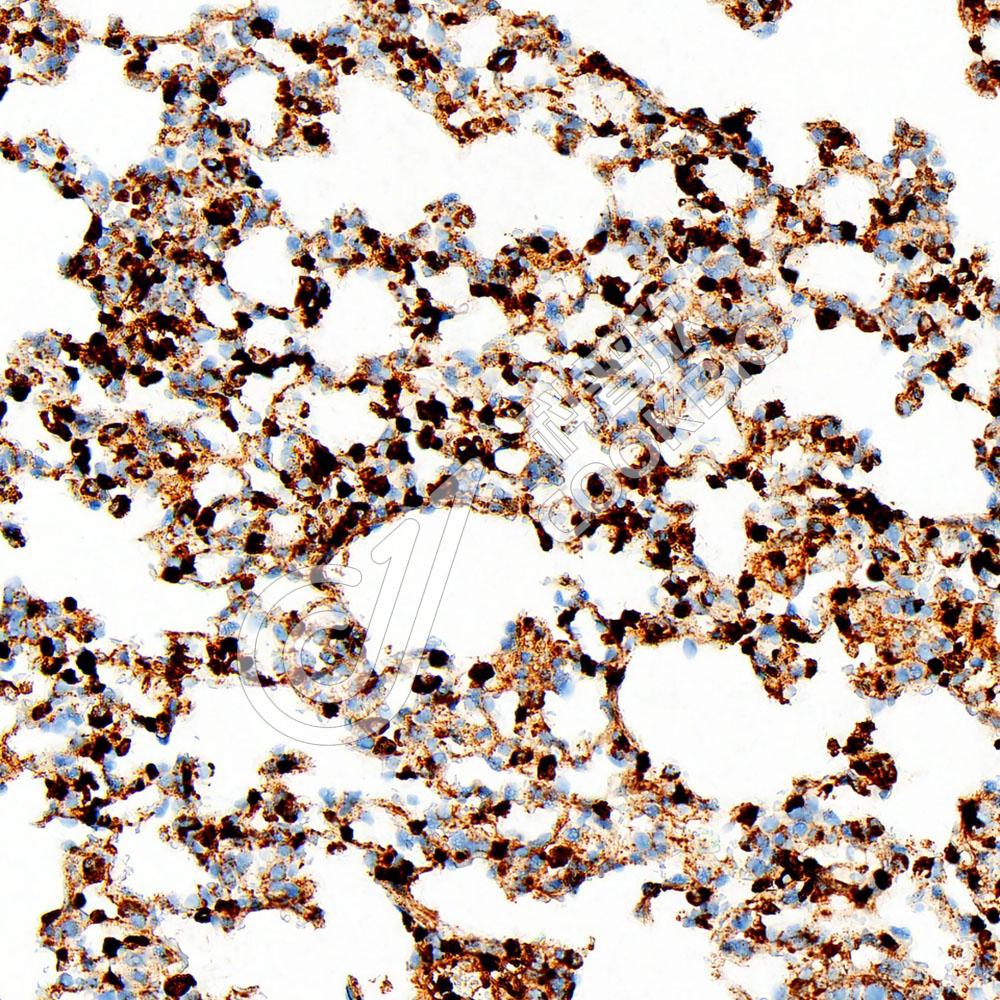

IHC检测CD63蛋白(货号 K546860).

样品: 小鼠lps(24h)肺诱导炎症模型, 4%多聚甲醛 (货号KSG1101) 固定12-24小时.

抗原修复: Tris-EDTA抗原修复液(pH 9.0) (KSG1203), 98℃, 20分钟.

—抗: 1: 1800稀释, 4℃ 孵育过夜.

二抗: S-vision免疫组化多聚二抗(山羊抗兔),即用型 (货号KB3906), 室温孵育20分钟.

样品: 大鼠lps(6h)诱导的肺部炎症模型, 4%多聚甲醛 (货号KSG1101) 固定12-24小时.